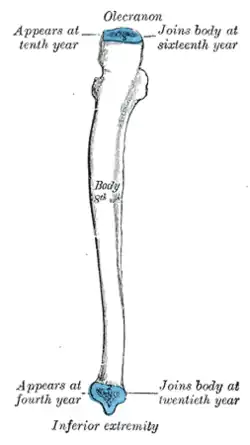

Plan of ossification of the ulna. From three centers.

Plan of ossification of the ulna. From three centers. -